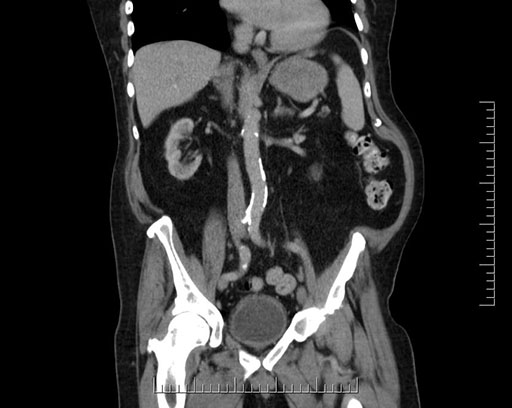

Whipple (pancreaticoduodenectomy) [case 7]

Imaging Analysis

Look through the patient's CT scan to identify any areas of concern for the necessary procedure.

Based on your CT findings, which issue(s) would give reason for "planned slowing down moment(s)" in this case?

Considering a standard Whipple procedure, what step(s) of the operation would you do differently in this case?